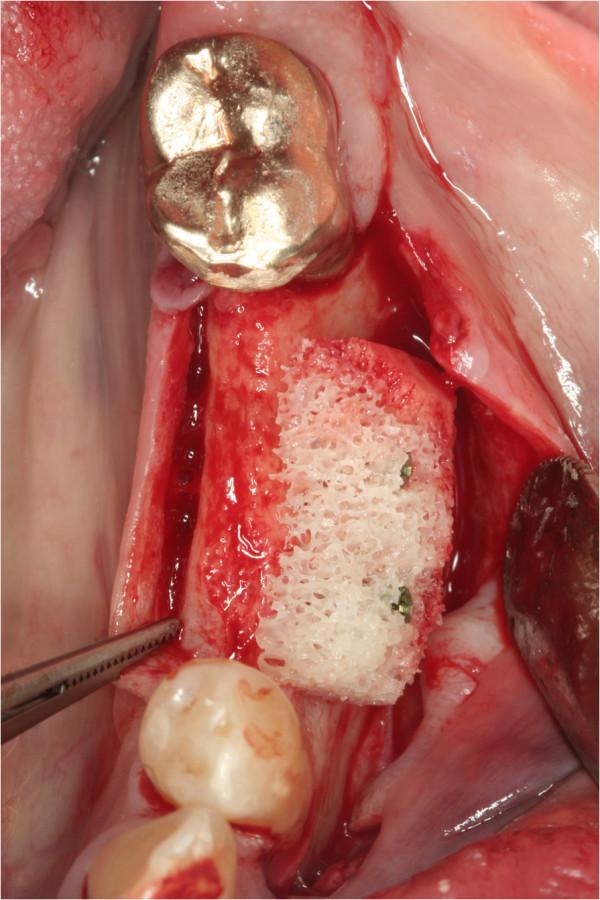

From 2003 to 2009, 67 patients underwent alveolar ridge augmentation and were enrolled in the study, 41 meet the inclusion criteria and 31 agreed to take part in the study. Patients were 18-69 years old (mean: 49.3 ± 13.8 years), and predominantly female. Patients received bone block grafts either autologous (n = 48) (AUBB) or allografts (ABB) (n = 19). Implants were inserted 4-7 months (autografts) or 5-6 months (allografts) after bone grafting. The Pink Esthetic Score (PES) as well as radiographic and subjective assessments were employed for the outcome analysis. The PES was assessed twice within one month based on digital photographic images that were randomly rearranged between evaluations by three independent, experienced investigators.

从 2003 年到 2009 年,67 名患者接受了牙槽嵴增高术,并被纳入研究,其中 41 名符合纳入标准,31 名同意参与研究。患者年龄 18-69 岁(平均:49.3±13.8 岁),主要为女性。患者接受骨块移植,自体(n=48)(AUBB)或同种异体(ABB)(n=19)。骨移植后 4-7 个月(自体)或 5-6 个月(同种异体)植入种植体。采用 Pink 美学评分(PES)以及影像学和主观评估进行结果分析。PES 在一个月内评估两次,根据数字摄影图像进行评估,评估之间图像随机排列,由三位独立、有经验的研究人员进行评估。